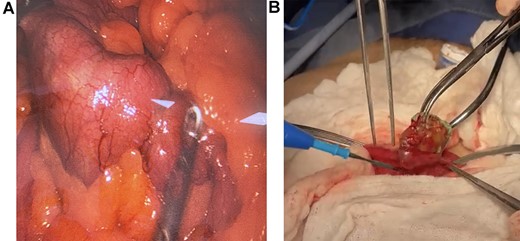

On laparoscopy, the full extent of the bowel was dilated, and the foreign body was discovered 1.80 m proximal to the ileocecal valve; then, the bowel was grasped and extracted through the umbilical port. After placing a skin protector, a 3-cm longitudinal incision on the antimesenteric side of the bowel was done, the foreign object was extracted, and the enterotomy was closed in a transverse fashion in two layers. No perforation, necrosis, or free fluid was found, and the remainder of the procedure was completed without complications (Fig. 2A and 2B).

(A) Laparoscopy, the foreign body is found in the bowel. (B) Extraction of the foreign body through enterotomy.

A 4 x 4.5 cm alginate dental mold shaped like a U was retrieved. Bowel obstruction due to accidental body ingestion was the final diagnosis (Fig. 3).